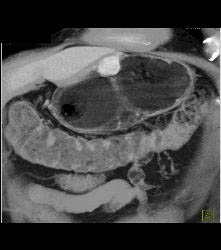

Glomus Tumor